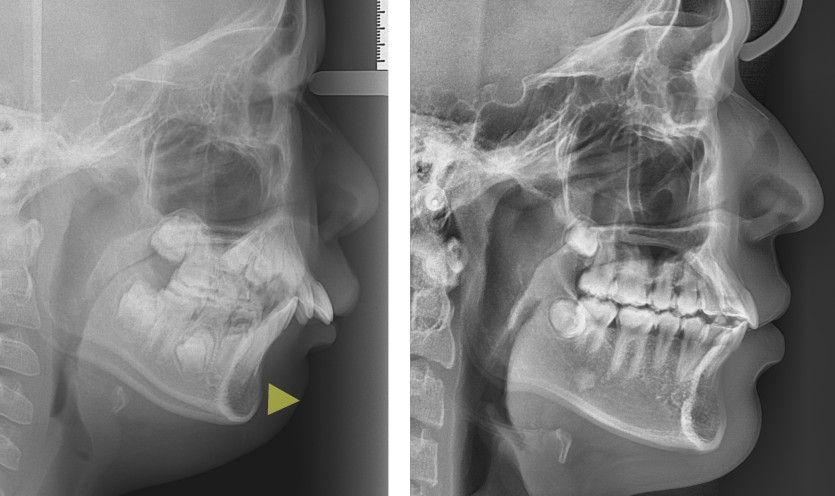

무턱의 성장조절 치료 151회

무턱을 지닌 청소년 환자들의 경우에는 안면 골격의 성장조절 치료를 진행할 수 있습니다.

사춘기는 성장이 급속하게 일어나는 시기이므로 상악의 성장을 헤드기어라는 장치를 통해 제한하고

바이오네이터라는 장치로 하악의 성장을 유도합니다.

헤드기어의 치료는 예측 가능하며 협조가 충분할 경우 상악의 성장 제한을 기대할 수 있으나

바이오네이터는 치료 반응이 좋을 수 있는 안모인지를 분류해야하며

하악의 성장이 적극적으로 일어난다기보다는 치조골의 변화를 통해 안면 골격의 편차를 극복하는 방법입니다.